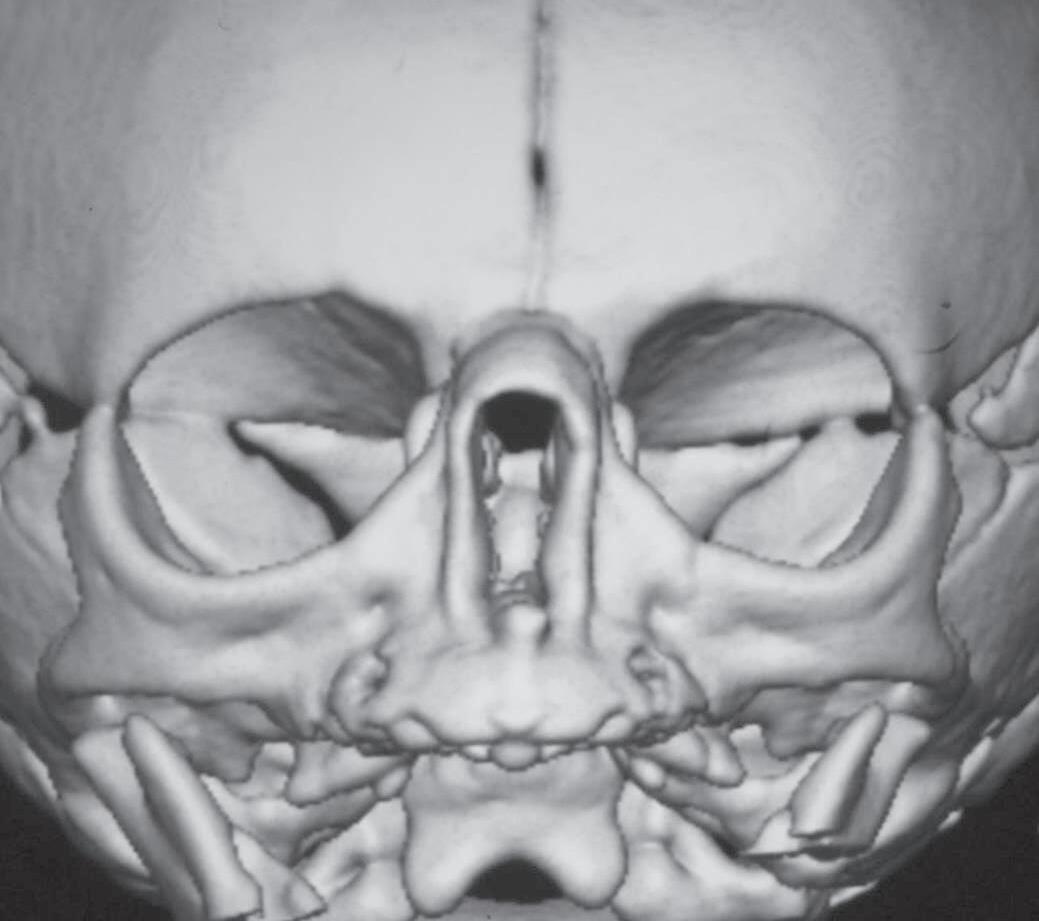

A tomografia computadorizada (TC) é o exame de escolha: valores abaixo de 11 mm são considerados sugestivos. Alguns autores mais rigorosos consideram o limite inferior de 8 mm (Fig. 1-1). A TC também avalia malformações associadas e estruturas como lâmina cribriforme e base do crânio.9 O diagnóstico diferencial deve incluir atresia de coanas, cistos, encefaloceles e tumores. A endoscopia nasal é útil para localização da obstrução.5,10

Além da correção esquelética, a ERM proporciona alargamento da base nasal, promovendo a redução da resistência ao fluxo aéreo e, consequentemente, aumento da ventilação nasal (Fig. 1-4).

9. Ao final da expansão, nova TC pode ser realizada para mensuração objetiva do ganho de espaço aéreo (Fig. 1-4), além da avaliação clínica (Fig. 1-8).

Apesar da eficácia da técnica de desgaste ósseo na abertura piriforme, seus potenciais riscos e complicações levaram ao aparecimento de outras opções terapêuticas. Vários estudos demonstraram que a atresia é maxilar, não se limitando ao piriforme, mas se estendendo por quase toda a cavidade óssea nasal.12,14 A expansão rápida da maxila, com dispositivo disjuntor e ancoragem esquelética por meio de miniparafusos, com sua fundamentação anatômica, biomecânica e funcional, é menos invasiva, proporciona uma expansão tridimensional eficaz ao longo de toda a fossa nasal, produzindo uma melhora funcional consistente nas vias aéreas superiores, que se mantém ao longo de todo o período de crescimento craniofacial (Fig. 1-9). Assim, a ERM credencia-se como técnica de escolha no tratamento da ECAP.15